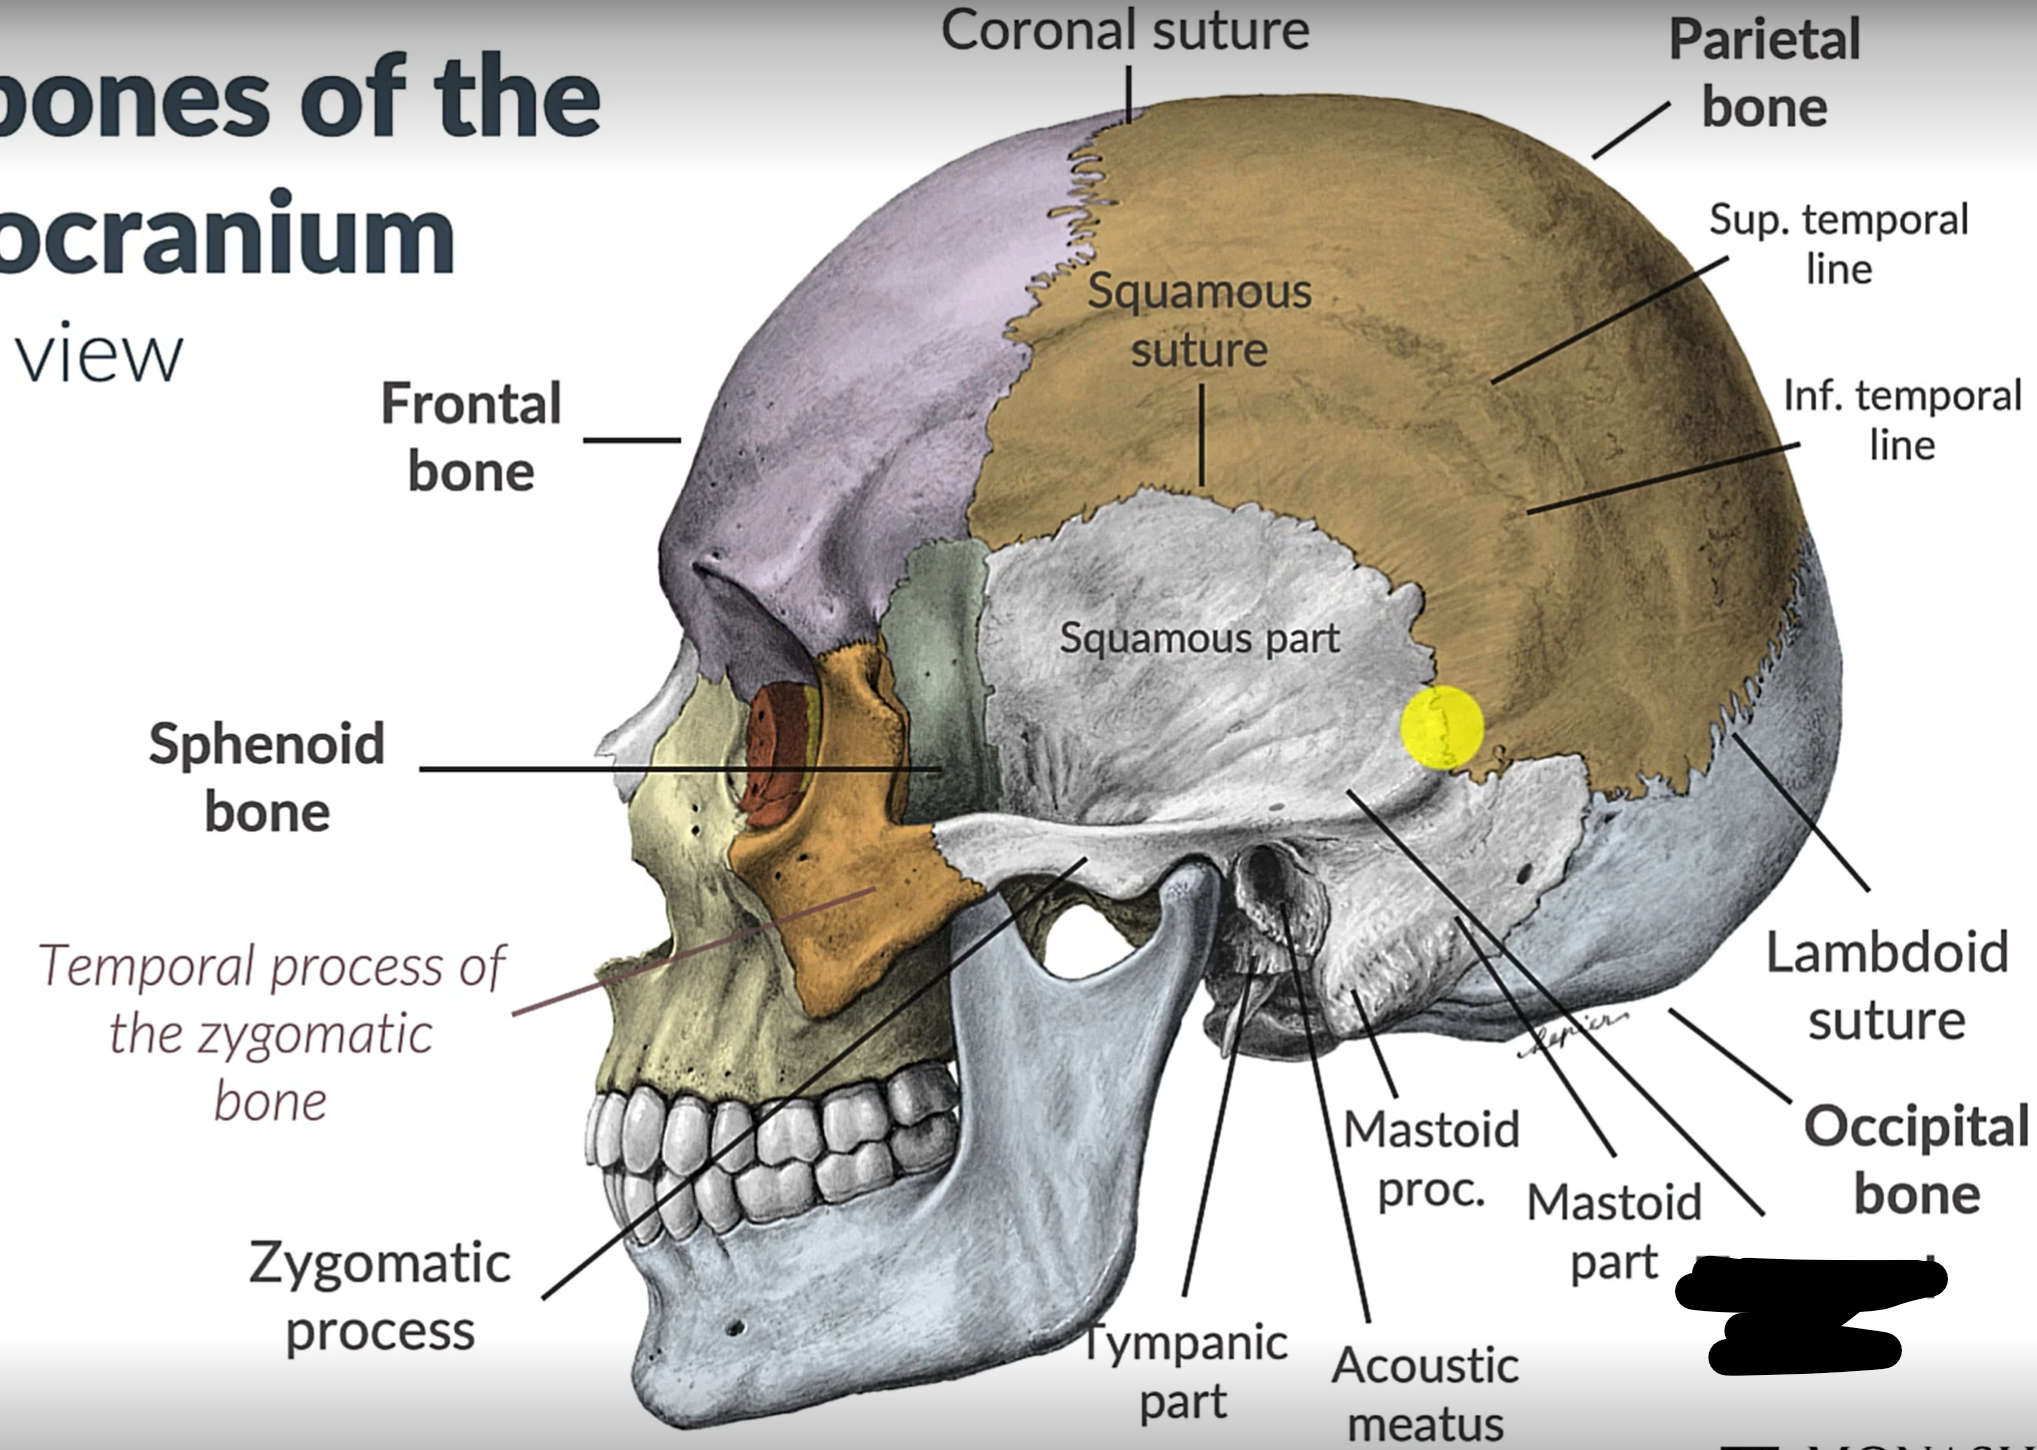

Parietal bone

Frontal bone

Temporal bone

Sphenoid bone

Zygomatic bone

Coronal suture

Squamous suture

Lambdoid suture

Occipital bone

Temporal bone

Zygomatic process

Sphenoid bone